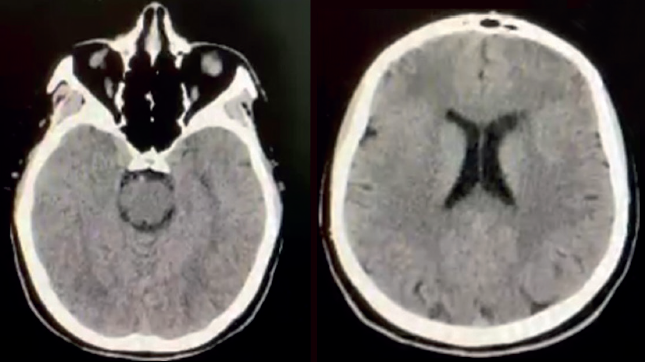

Se completó el estudio con una resonancia magnética de cráneo axial en T1, donde no se observó evidencia clara de alteraciones estructurales que pudieran explicar o complementar el cuadro clínico presentado (figura 1).

Con base en el Manual diagnóstico y estadístico de los trastornos mentales (5ª edición, DSM-5)6, se estableció que el cuadro cumplía los criterios diagnósticos para esquizofrenia, es decir: delirios, alucinaciones, comportamiento desorganizado, síntomas negativos, durante un lapso mayor a 6 meses, con disfunción social, cognitiva y familiar, excluyendo otras patologías psiquiátricas/médicas o sustancias que lo explicaran6.